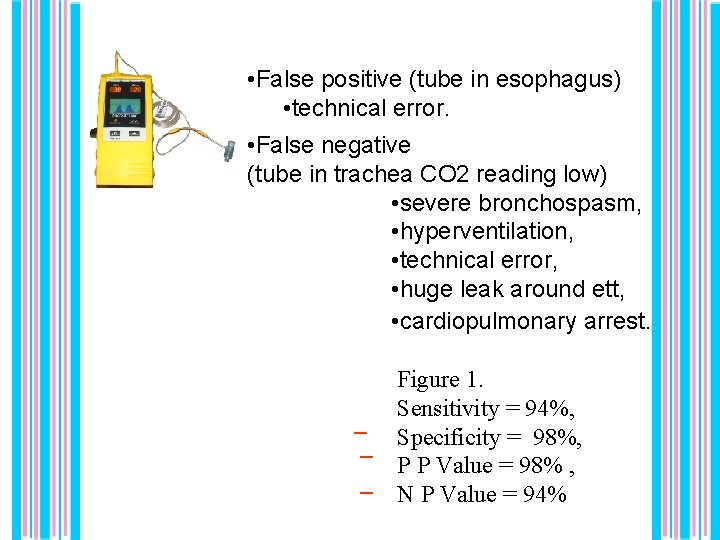

• False positive (tube in esophagus) • technical error. • False negative (tube in trachea CO 2 reading low) • severe bronchospasm, • hyperventilation, • technical error, • huge leak around ett, • cardiopulmonary arrest. _ _ _ Figure 1. Sensitivity = 94%, Specificity = 98%, P P Value = 98% , N P Value = 94%